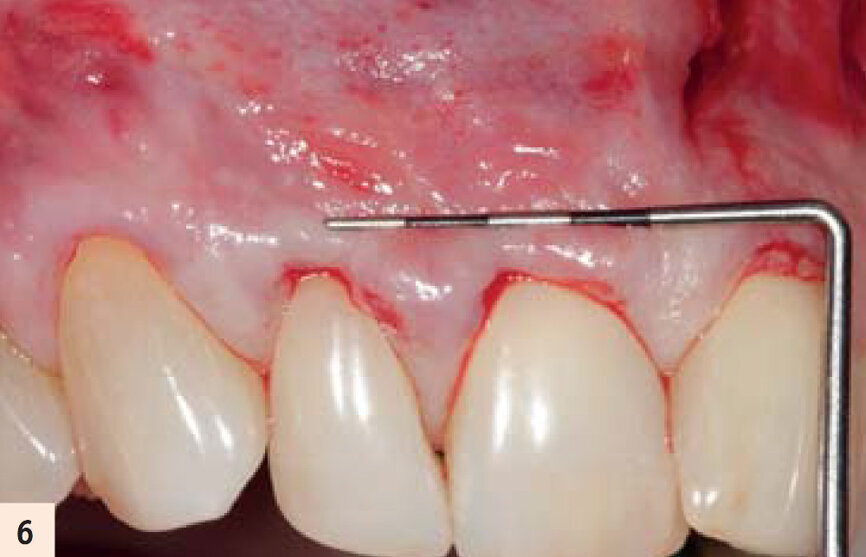

Incision et relâchement du lambeau. Incision vestibulaire pour accès sous périostée (incision muqueuse horizontale) permet une dissection horizontale de pleine épaisseur. Le relâchement total du lambeau permet au clinicien d’éviter une pression incontrôlée du lambeau sur les membranes A-PRF et permet le positionnement coronaire complet et passif des tissus mous

L’incision muqueuse verticale permet l’instrumentation horizontale (mesio-distale) et apico-coronaire d’un lambeau de pleine épaisseur, ce qui entraine le relâchement total et le déplacement coronaire passif du complexe muco-gingival papillaire (Figs. 5, 6).